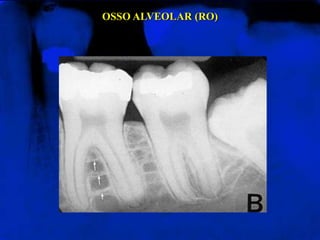

OSSO ALVEOLAR (RO)

Chamado também de osso trabecular ou osso esponjoso.

Apresenta-se como uma estrutura trabecular radiopaca,

limitada por espaços medulares radiolúcidos

OSSO ALVEOLAR (RO) Chamadotambém de osso trabecular ou osso esponjoso. Apresenta-se como uma estrutura trabecular radiopaca, limitada por espaços medulares radiolúcidos